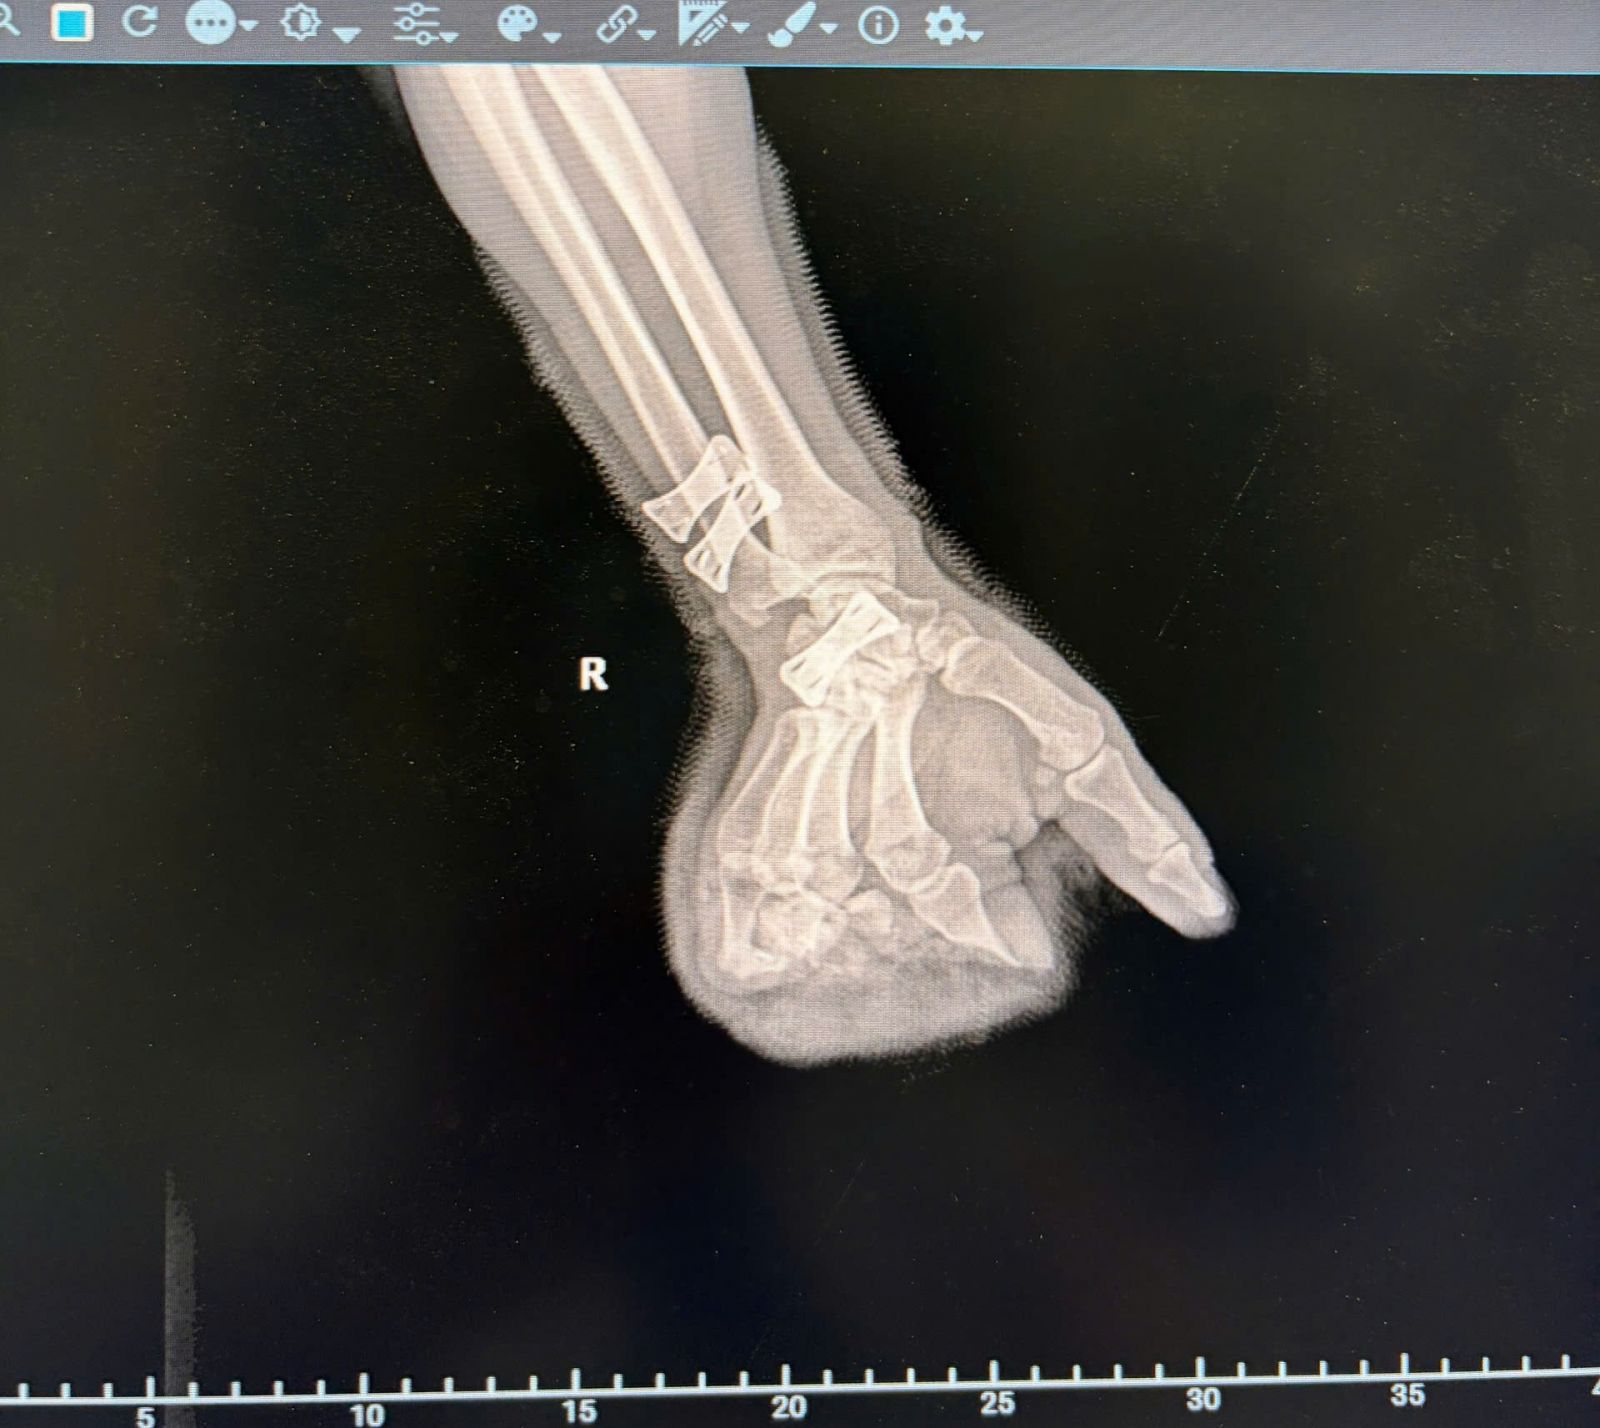

Ngay sau khi tiếp nhận, các bác sĩ đã nhanh chóng xử trí cấp cứu: truyền dịch, dùng kháng sinh, tiêm phòng uốn ván, đồng thời thực hiện các xét nghiệm cần thiết và chụp X-quang để đánh giá mức độ tổn thương.

Qua thăm khám và hội chẩn, xác định các ngón tay tổn thương nặng, không còn khả năng bảo tồn, người bệnh được chỉ định phẫu thuật cấp cứu sửa mỏm cụt các ngón 2, 3, 4 bàn tay phải. Ca phẫu thuật do BSCKI Cao Việt Tiệp thực hiện được tiến hành khẩn trương, đảm bảo xử lý tổ chức dập nát, tạo hình mỏm cụt, hạn chế nguy cơ nhiễm trùng và giúp người bệnh thuận lợi hơn trong sinh hoạt về sau.